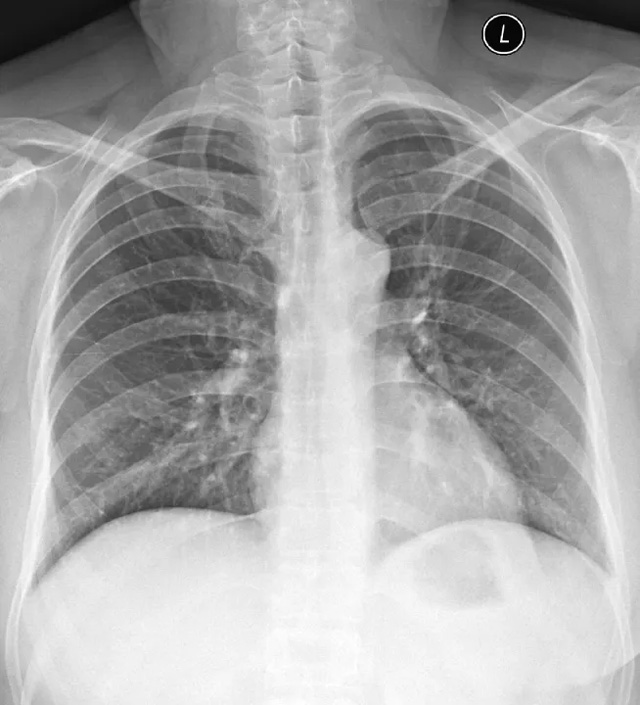

X線定位真空輔助旋切術是對臨床觸診和B超檢查均為陰性而X線片顯示的微小病變在X線立體定位引導下,將真空旋切刀置入乳腺可疑病灶區(qū)進行旋切及組織病理學檢查的一種乳腺微創(chuàng)新技術。